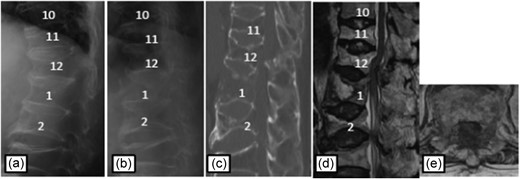

Plain radiographs on initial assessment (a) and on admission (b); Sagittal CT image (c) showing the hyperextension fracture at L1 and dislocation of it; MRI T2-weighted image (d, e) showing the severely compressed spinal cord at T12 level.